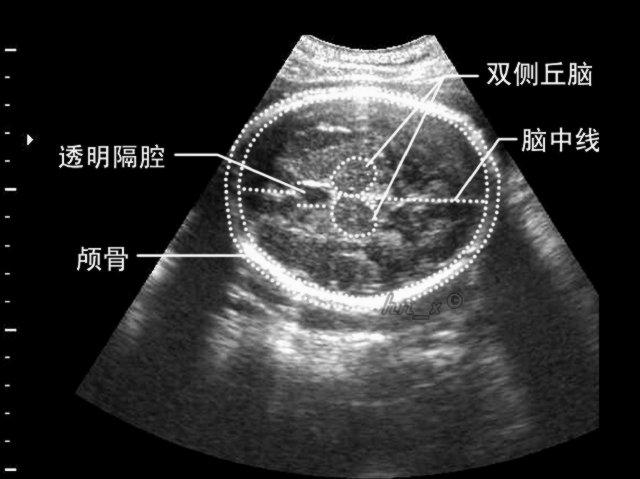

切面,见图3-2-22;②透明隔和尾状核切面,见图3-2-23;③丘脑冠状切面